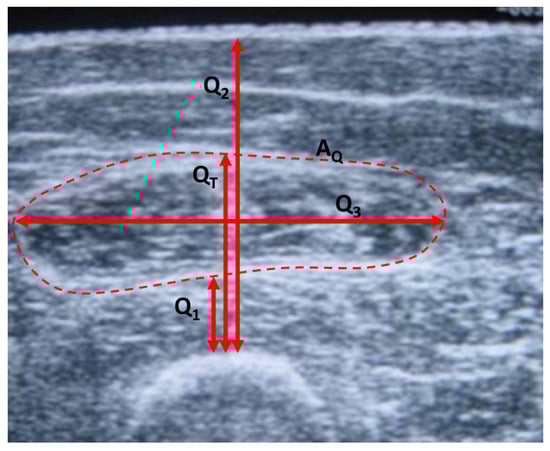

These results highlight the need to investigate techniques and methods that allow the objective evaluation of muscle atrophy, which may be of interest not only in the diagnosis but also in the evaluation of the results obtained with the treatment or therapeutic interventions, such as muscle training applied in respiratory rehabilitation [14,16,17,18]. In the search for an objective marker of muscle deterioration, the cross-sectional area of the quadriceps ( A Q ) [13,14,19,20] has been used. The decrease in this area, which can be evaluated by ultrasound or computed tomography, has been related to a worse prognosis of the disease [13,14,19,20].

Another marker used in many studies to objectively evaluate muscle atrophy in the lower limbs is the thickness of the quadriceps ( Q T ), calculated as the width of the muscle from the femur to the external fat surface, and measured at the midpoint of the line joining the knee to the greater trochant [21,22,23]. Figure 1 shows an example of Q T and A Q on an image of the quadriceps made by ultrasound. These parameters have been considered as indicators of the health status of patients with COPD [23,24] and predictors of complications and exacerbations [22,25].

• Measurements: The reference measurements of muscle dimensions were carried out by ultrasound using an Aloka SSD-900 Ultrasound Machine (ALOKA Co. Ltd., Tokyo, Japan). Procedure: The patient was placed in a supine position, with a rolled towel under the popliteal fossa to relax the thigh. The transducer was placed with the long axis perpendicular to the longitudinal axis of the rectus femoris muscle, at the midpoint between the anterior superior iliac spine and the superior edge of the patella. Using the device’s software, the area and dimensions of different muscle sections were estimated, recording the data for subsequent analysis. The following measurements were obtained, referring to the image in Figure 1: thickness of the vastus intermedius ( Q 1 ), length from the femur to the upper limit of the rectus femoris ( Q T ), length from the femur to the skin ( Q 2 ), transverse thickness of the rectus femoris ( Q 3 ) and area of the rectus femoris ( A Q ). Isometric strength is defined as a static contraction without a change in muscle length. To measure this strength, the subject was seated and with a knee flexion of 90°. The knee was extended against static resistance and the isometric quadriceps strength F i s o M was established using an isometric dynamometer. The isotonic force F i s o T was evaluated through the 1RM test, defined in this case as the maximum weight that an individual sitting and with knee flexion of 90º can lift in a single repetition. For bioimpedance measurements, the adapted device described in the present work was used following the measurement protocol described in Section 2.1.

Although the parameters Q 1 , Q 2 and Q 3 are not usually used in the literature as indicators of the health status of patients with COPD, these parameters are also included in the present work to provide additional information on the structural components of the quadriceps muscle. In this way, Table 4 shows the results of the correlation analysis of the parameters Q 1 , Q 2 and Q 3 , respectively, with respect to the bioimpedance parameters, and for each of the study groups. Except in Group I, the bioimpedance parameters related to resistive values and membrane capacity also show good correlations with Q 1 and Q 2 . This result was expected since these parameters correspond to other structural parameters of the quadriceps muscle similar to the dimensions described by Q T and A Q . In Group I, C M is the parameter that shows the highest correlation, but it does not have sufficient statistical significance. As previously mentioned, this fact may be due to the small number of measurements in this group. It is also worth noticing the high correlation found in the parameter Q 2 with respect to τ in Group I, 0.84, with statistical significance. On the other hand, there is a remarkable lack of correlation of the bioimpedance parameters with the parameter Q 3 , which has been obtained in the direction transverse to Q 1 and Q 2 as can be seen in Figure 1.

Figure 1. Thickness Q T and the area A Q on an ultrasound image of the quadriceps.